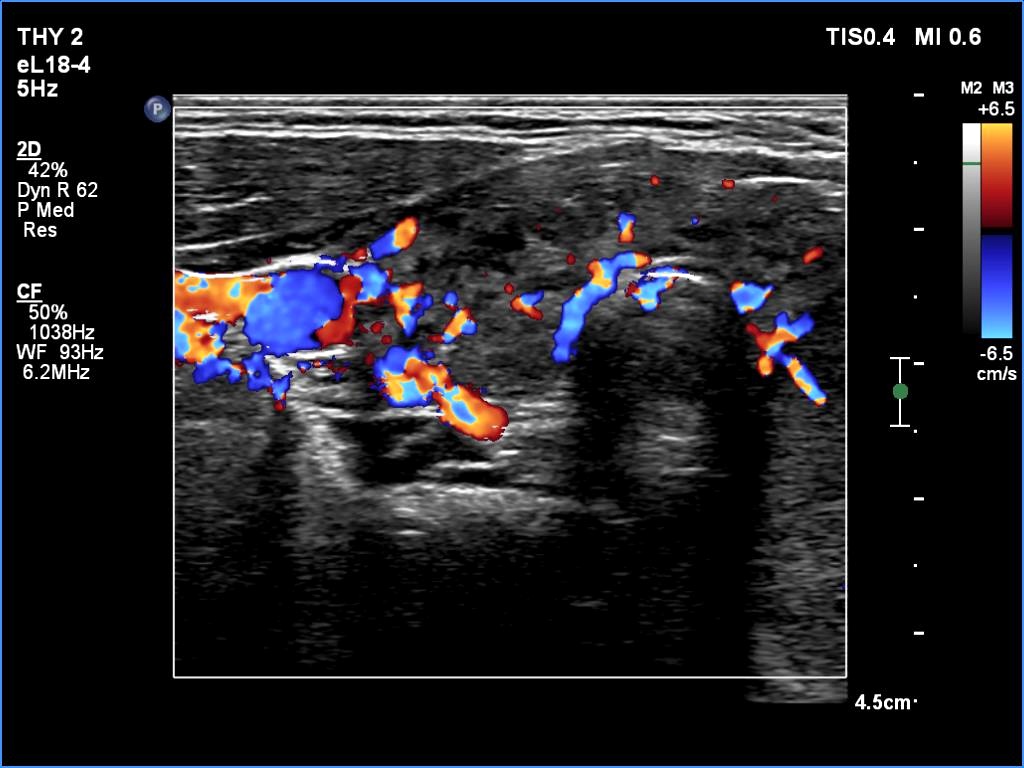

The echogenicity of the nodule - case 365 (ultrasonographic picture 3)

Five years after the first examination

Right lobe, transverse scan, color Doppler mode. The vascularity is a bit increased.